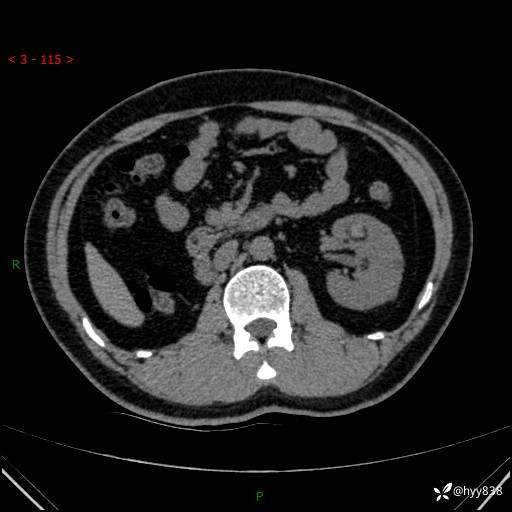

患者性别:男

患者年龄:28岁

简要病史:右肾肿瘤术后,常规复查

辅助检查:CT

临床诊断:右肾肿瘤术后

腹部CT+颅脑CT平扫